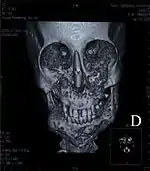

Рентгенологическая картина

Рентгенологическим методом при херувизме можно установить близкое к симметричному двустороннее вздутие тела и углов нижней челюсти, неравномерное истончение кортикального слоя, множественные очаги разрушения костной ткани в форме кист разных размеров. На верхней челюсти может возникать вздутие в переднем отделе с аналогичной структурой. На боковых участках верхней и нижней челюсти зоны деструкции всегда разграничены участком неизменённой кости[2].